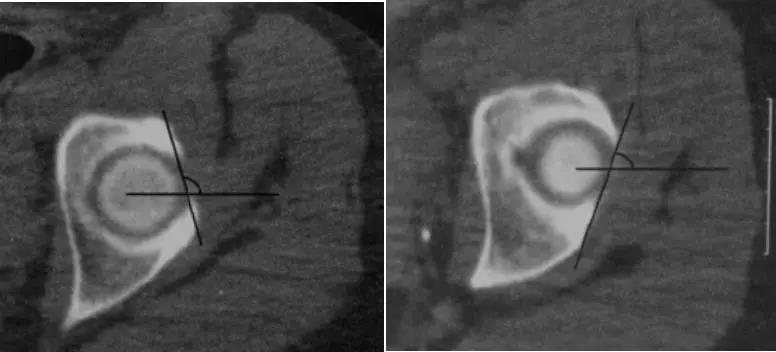

钳夹撞击型FAI▼

- 横断面显示髋臼后倾:正常髋臼连线与水平线呈钝角;呈锐角,提示髋臼后倾。